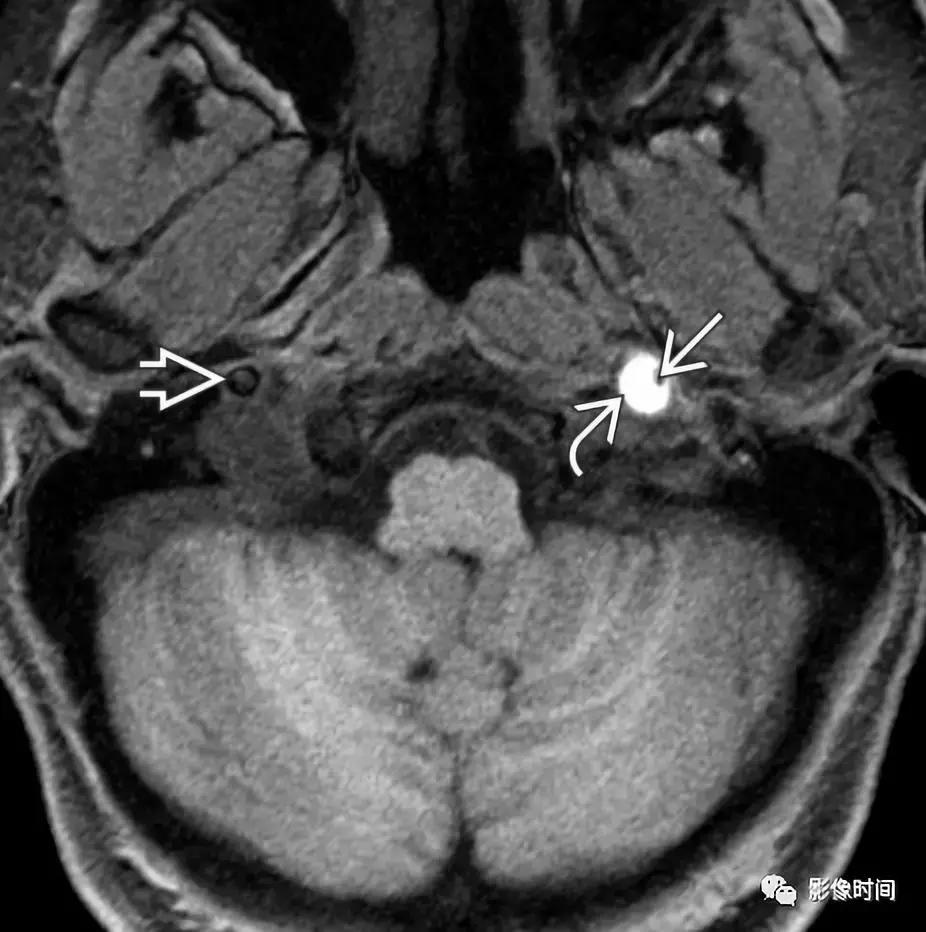

(2)神经纤维瘤:20-30 岁青年患者多见,10% 神经纤维瘤与发生于神经纤维瘤病,根据形态分为弥漫型、丛状、局灶型,纵向及梭形生长,特征性表现为「靶征」或「鱼眼征」,是指病灶中心的 T2WI 低信号。

T1WI 显示病灶相对于肌肉呈低信号,T2WI 病灶呈高信号,病灶包绕左侧颈内动脉 (i)。注意此病变的特征「鱼眼」或「靶」外观(黑色箭头)。